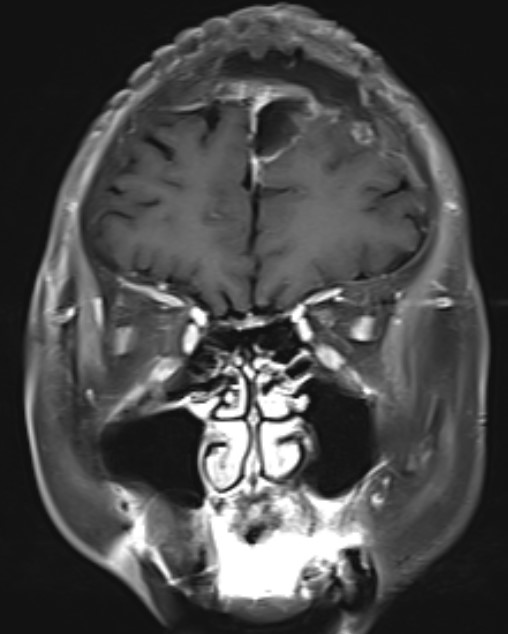

患者女性,62岁,因头晕一月在外院检查头部MR发现左额镰窦旁肿瘤来我院

手术精要:1 肿瘤基底在大脑镰,切口过中线,骨窗显露矢状窦边缘;2  翻开硬膜及切除肿瘤时注意肿瘤周围尤其是肿瘤表面的引流静脉的保护;3 肿瘤切除策略锐性分离,分块切除,优先阻断肿瘤基底血供

术后病理提示脑膜瘤,混合型

患者恢复良好无神经功能障碍,一周顺利出院